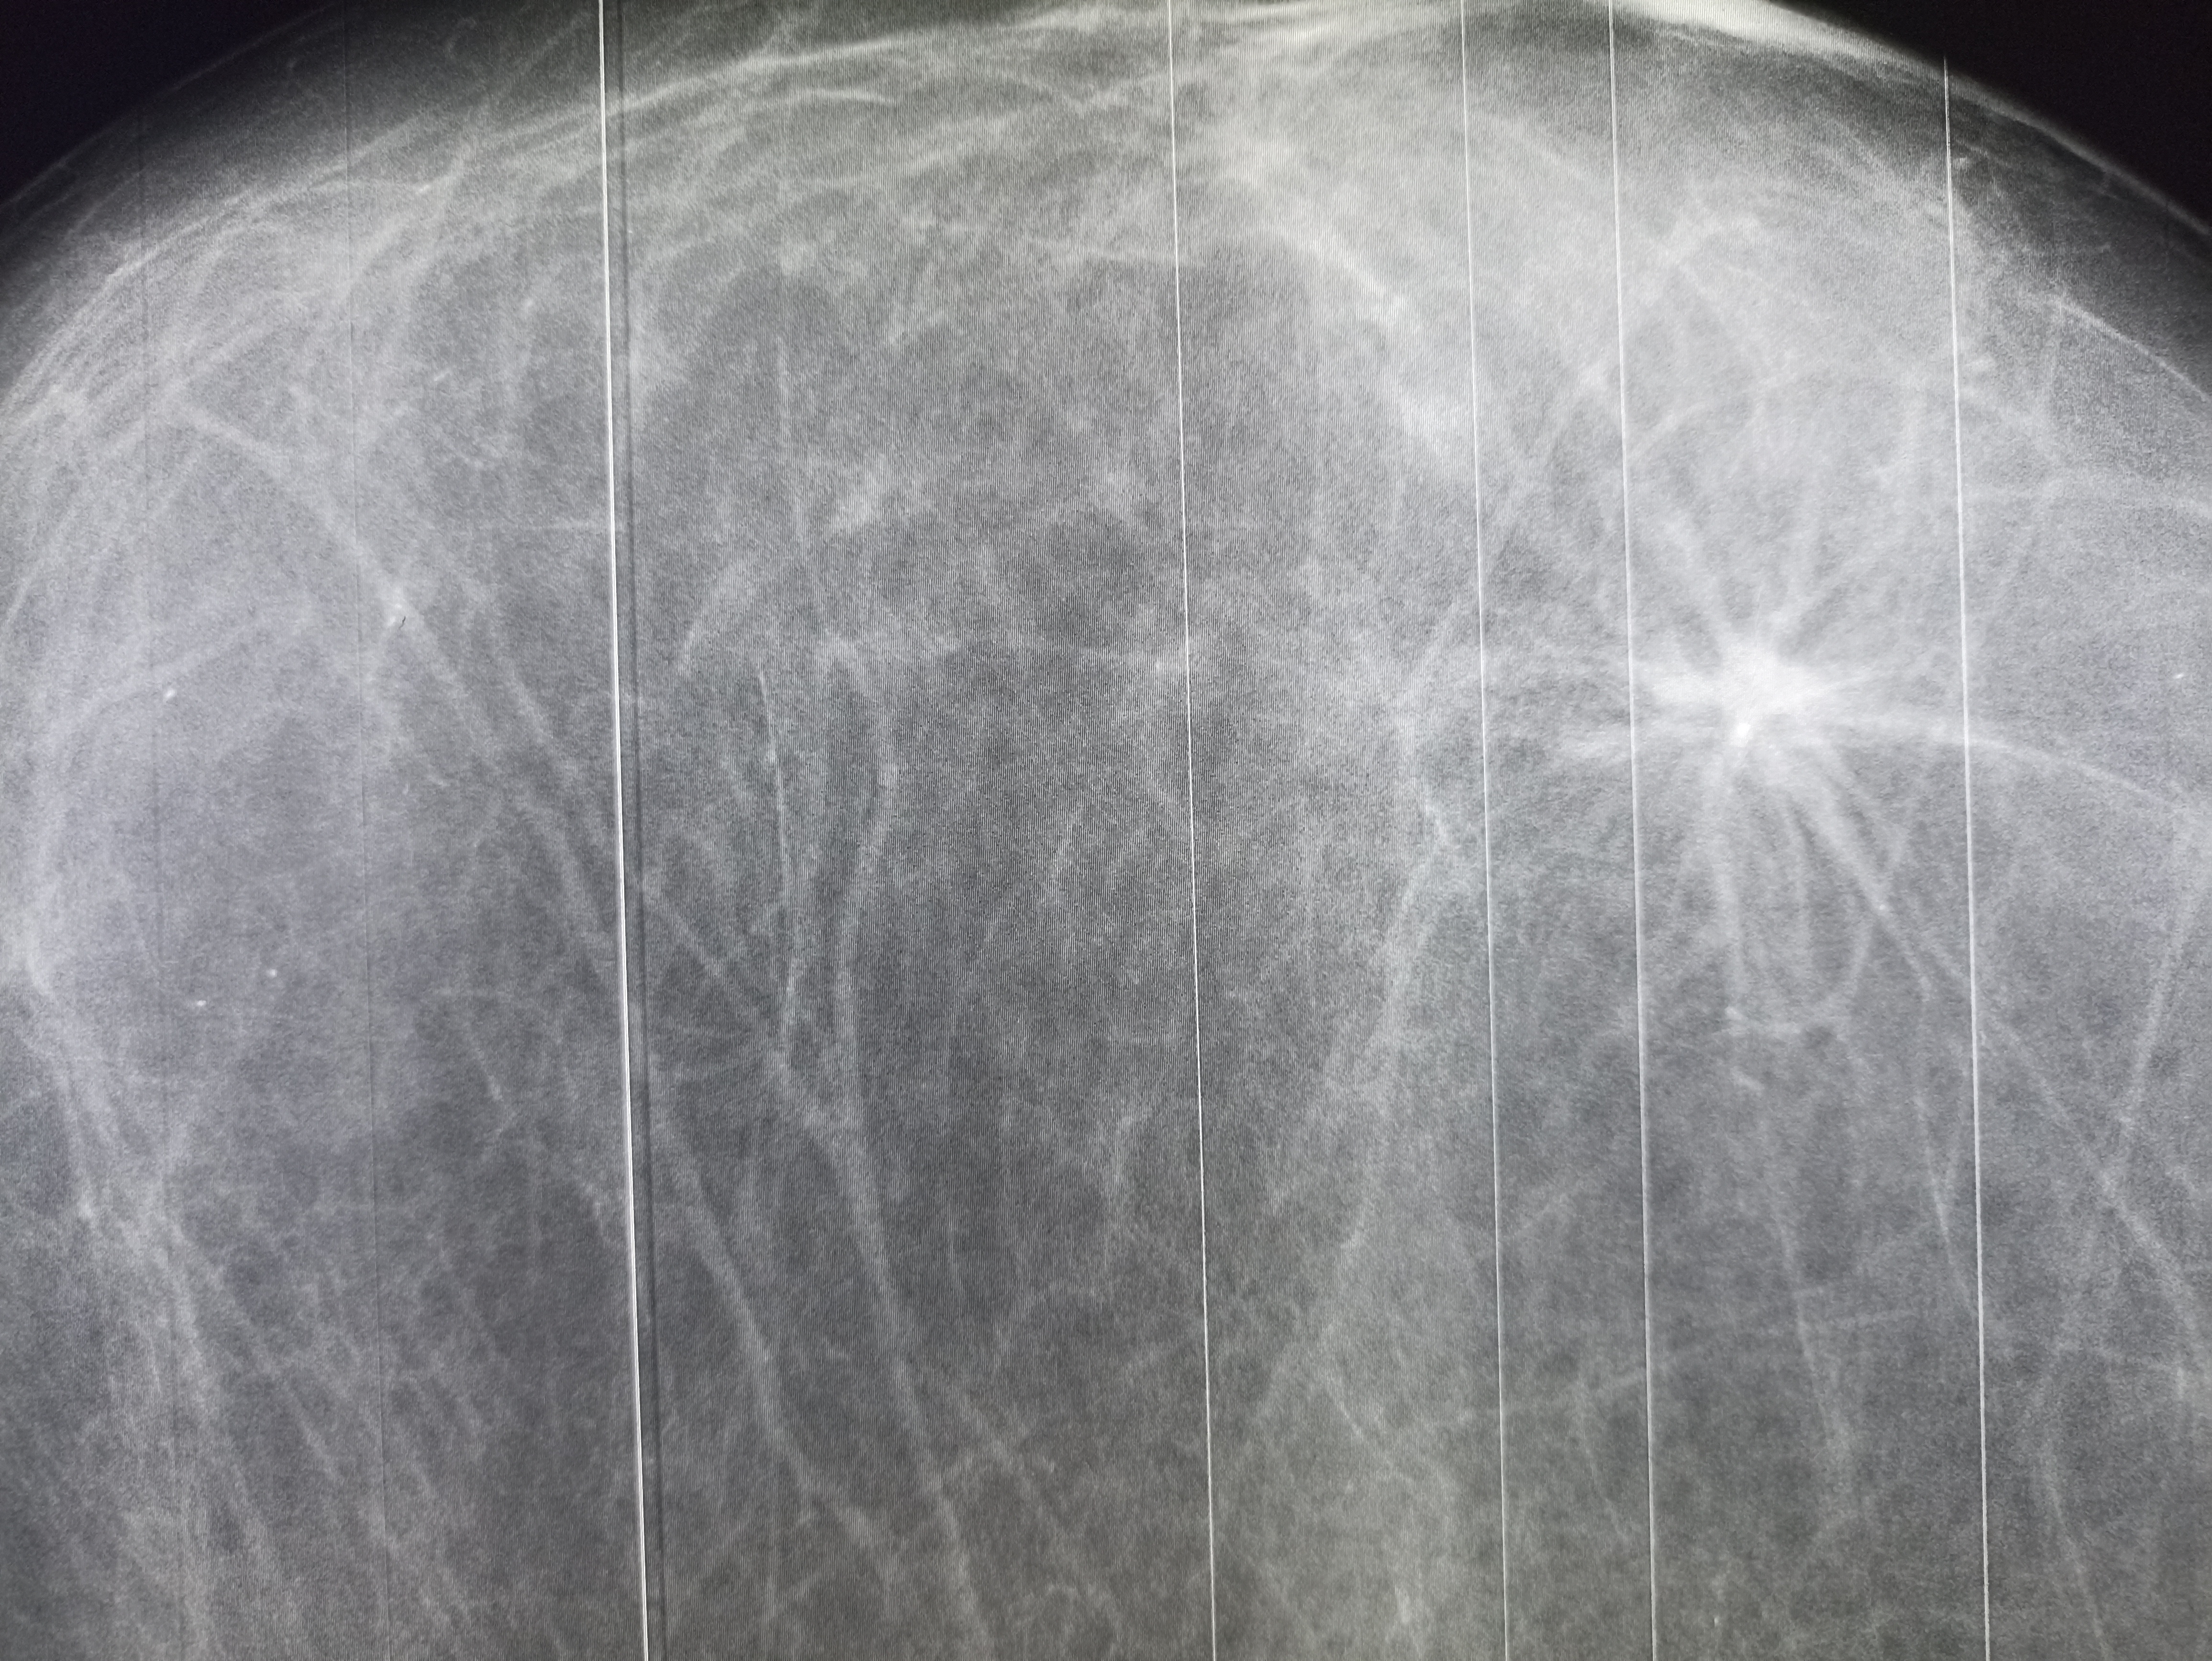

IMG20251208130343.jpg

Где пиздецома?

>>327475146

Сосуды забиты справа посередине

>>327475345

Это не сосуды, это пищдецома в сиське, скопее в сего рак. Но это не точно, надо дообследовать

>>327474838

Округлое образование с проветлением в центре в нижней доле правого лёгкого. На тубик не похоже по локализации, мб абсцесс в стадии рассасывания

>>327475403

Пока чо-то отрицательное пришло, но на консультацию к иефекционисту записали.

Абсцесс да там еще сверху в левом лешком полость

>>327474923

Ателектаз слева?

Аноним 09/12/25 Втр 08:22:33 #42 №327475511

Хм, так понимаю увеличены сердце и магистральные сосуды, которые дают такую мощную тень?

>>327475506

И опухоль тож, там рак желудка первичный

Сердце почти нк расширено, там рак с первичным очагом в желудке.

Аноним 09/12/25 Втр 08:30:34 #49 №327475664

>>327475631

Центральный рак лёгкого справа?

>>327475724

Метастазы, из желудка

Я про то, на снимке сами метастазы где? В районе бронхов справа?

Аноним 09/12/25 Втр 08:39:09 #62 №327475829

>>327475819

В левом легком, в средостении в периферии ателектаз.